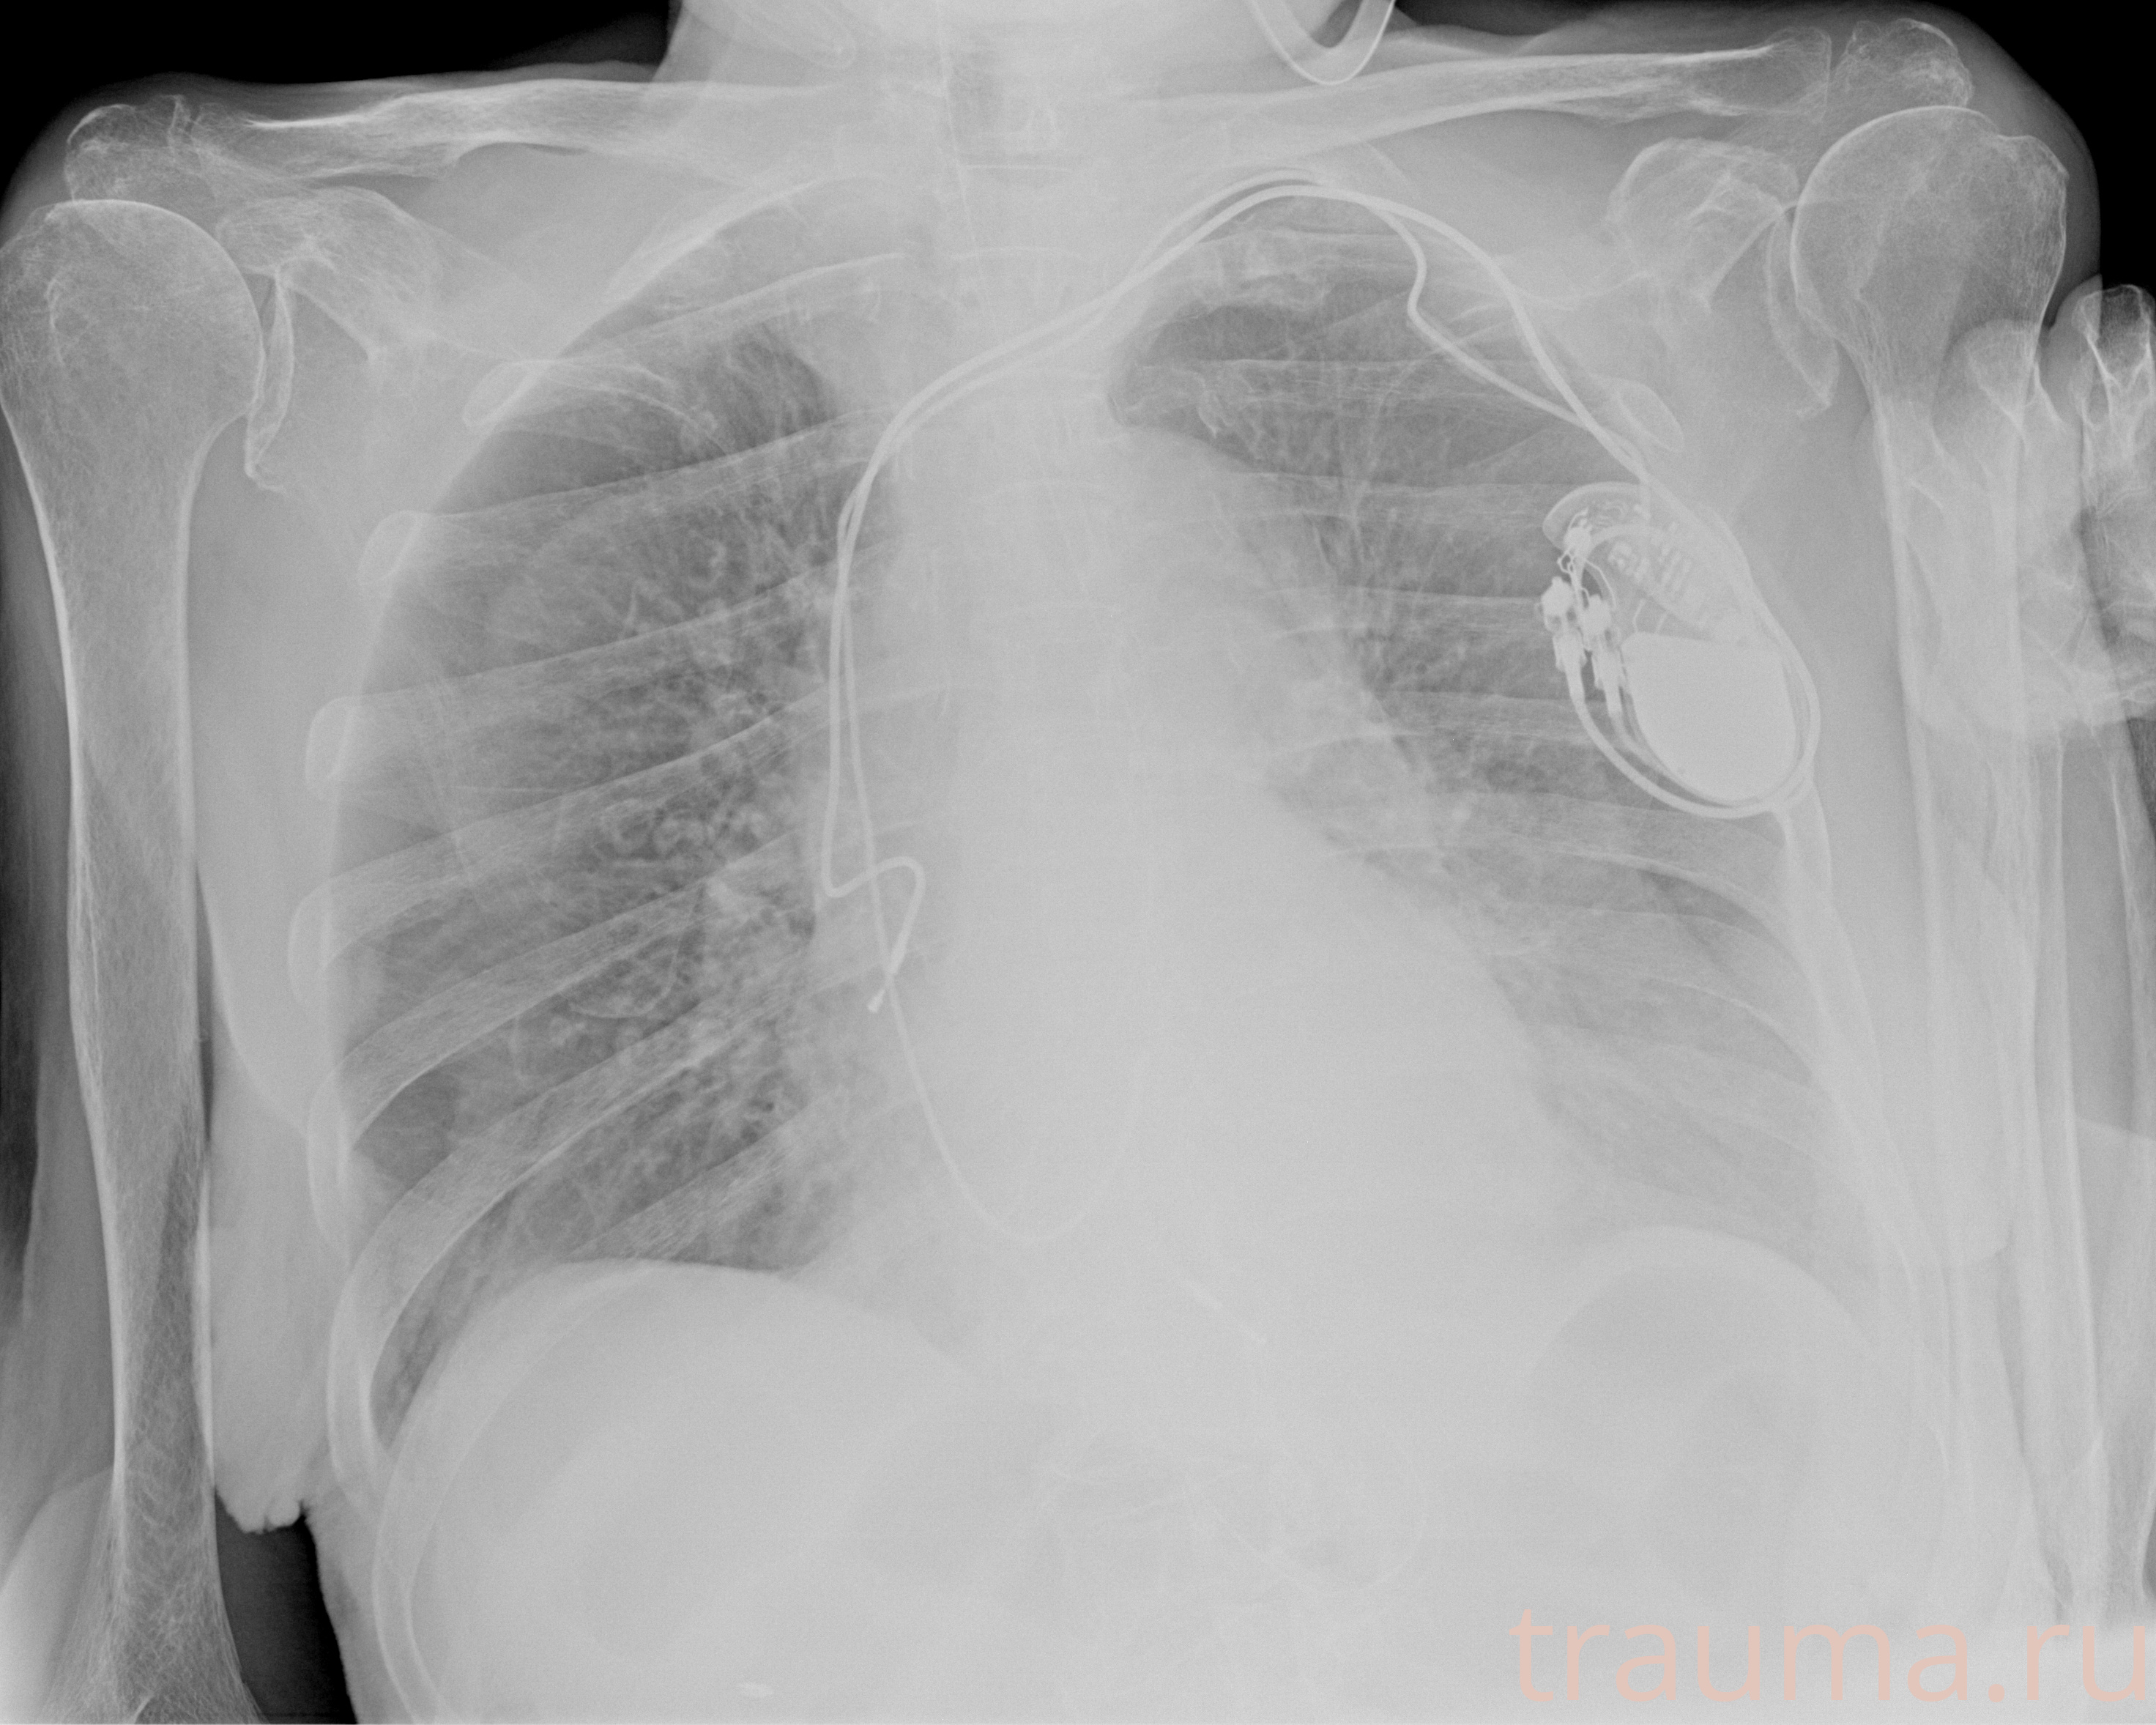

Рентген на дому: по вашему адресу приезжает врач-рентгенолог, травматолог-ортопед с мобильным рентгеновским аппаратом, проводит диагностику травмы или заболевания, делает необходимые рентгенограммы, дает рекомендации по дальнейшему лечению. Получить качественные снимки в домашних условиях возможно благодаря уникальной методике, разработанной МосРентген Центром для института  Склифосовского